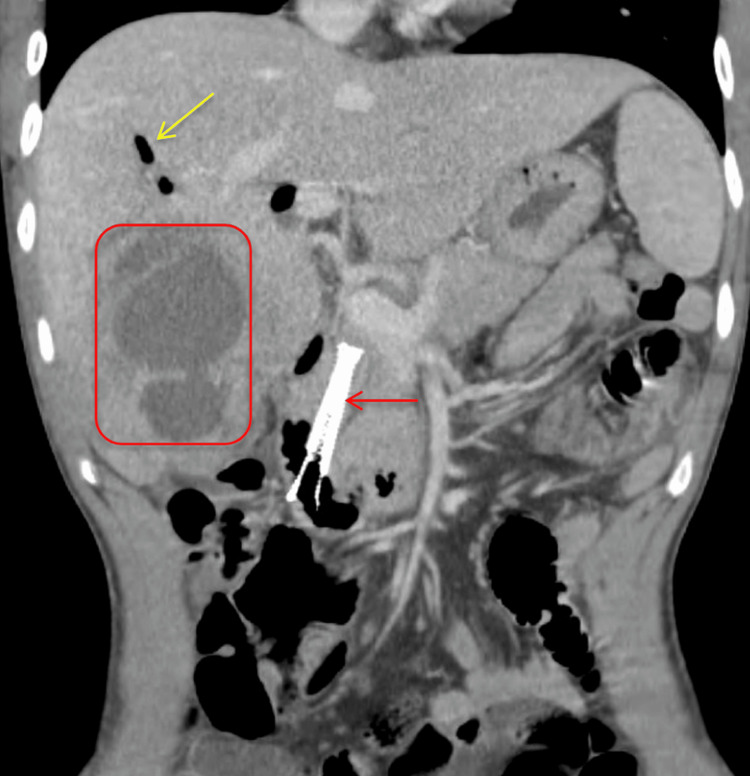

Post-procedure, the patient developed improved jaundice and abdominal pain and was able to tolerate a regular diet with discharge home on the fifth post-procedure day. He re-presented three weeks later due to progressive cramping abdominal right upper quadrant (RUQ) pain, nausea, and bilious emesis. An abdominal ultrasound and CT demonstrated a large 8.5 cm liver abscess in the right hepatic lobe, with a posterior defect in the hepatic margin of the gallbladder wall (Figures 4–6). There was noted septic thrombosis of the right portal venous system. He underwent emergent CT-guided percutaneous transhepatic drainage of the liver abscess, with cultures demonstrating Streptococcus anginosus. He was initiated on empiric IV piperacillin-tazobactam, followed by a transition to a four-week course of oral amoxicillin-clavulanate 875-125 mg twice daily after sensitivity results were completed. He was initiated on therapeutic enoxaparin followed by conversion to oral apixaban for a planned six-month course for portal thrombosis. Repeat CT imaging demonstrated stable portal thrombus without extension or enlarging hepatic abscess. He was discharged home with planned interval endobiliary stent removal and delayed interval cholecystectomy. No complications or recurrent symptoms were observed during the patient’s follow-up after discharge.